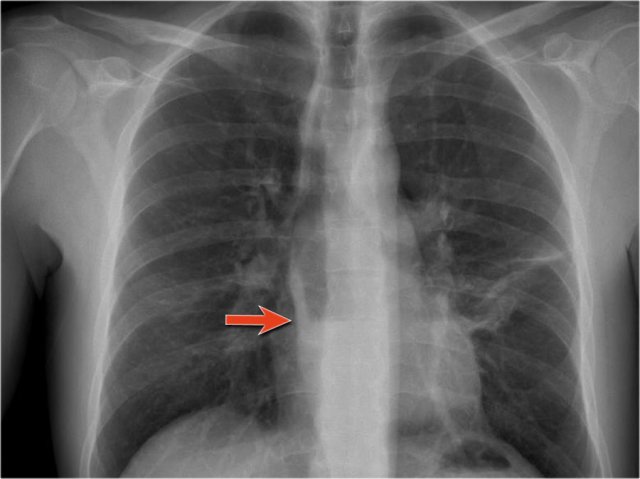

An important mediastinal-lung interface to look for is the azygoesophageal line or recess (arrow).

Azygo-esophageal recess

The azygo-esophageal recess is the region inferior to the level of the azygos vein arch in which the right lung forms an interface with the mediastinum between the heart anteriorly and vertebral column posteriorly.

It is bordered on the left side by the esophagus.

Deviation of the azygoesophageal line is caused by:

- Hiatal hernia

- Esophageal disease

- Left atrial enlargement

- Subcarinal lymphadenopathy

- Bronchogenic cyst

Notice the deviation of the azygoesophageal line on the PA-film.

It is caused by a hiatal hernia.

The arrow point to the barium contrast within the hiatal hernia.